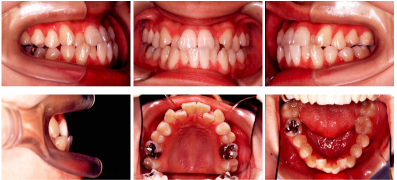

• 口腔内写真と顔面写真

• _